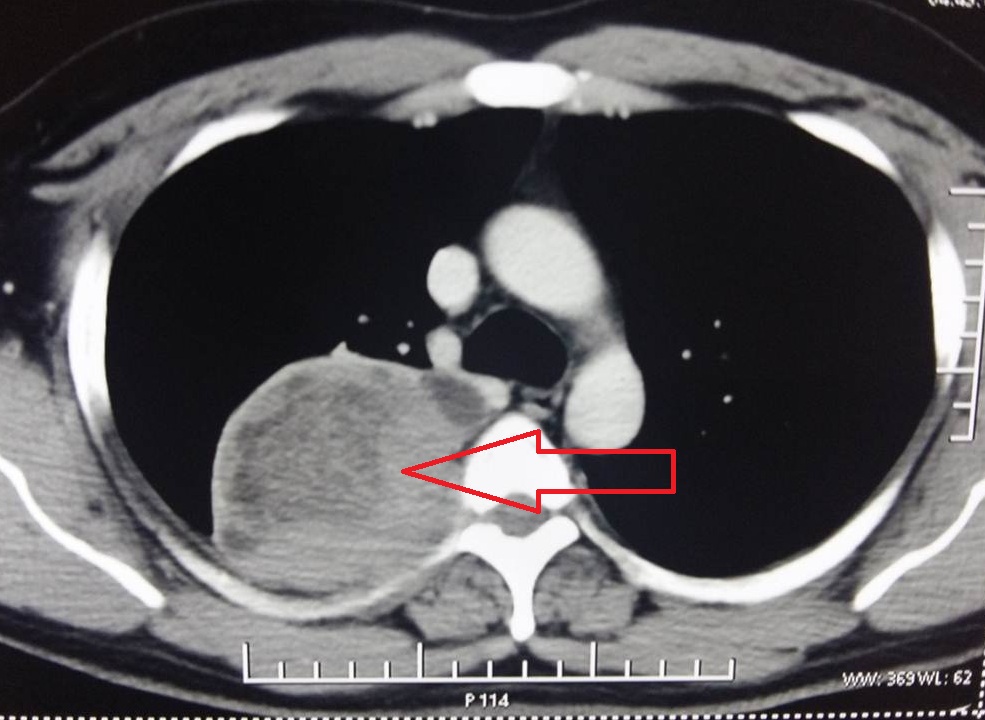

- Figure 4. CECT Thorax showing a heterogeneous mass in the posterior aspect of the right upper lobe eroding the rib margin